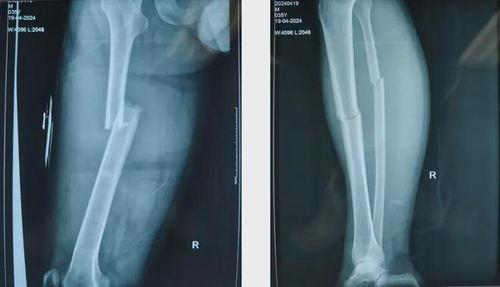

1. 股骨骨折:股骨骨折是常见的骨折类型,通常发生在老年人或交通事故中。

2. 胫腓骨骨折:胫腓骨骨折多发生在踝关节扭伤或跌倒时。